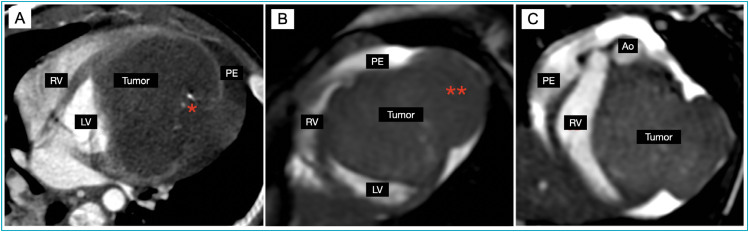

Case description: A 5-month-old male infant was admitted to the pediatric emergency department with acute viral bronchiolitis requiring hospitalization. He presented a detectable respiratory syncytial virus in oropharyngeal swab, blood test with lymphocytosis and a chest radiography revealed cardiomegaly. Further cardiologic testing was performed detecting elevation of cardiac biomarkers, an electrocardiogram with alteration of left ventricular repolarization and echocardiogram with a heterogeneous mass in the left ventricular, with areas of calcification. A chest angiotomography suggested rhabdomyosarcoma or cardiac fibroma and a magnetic resonance showed a mass, with characteristics suggesting fibroma. The final diagnosis was made after two cardiac catheterizations for biopsy of the lesion, confirming cardiac fibroma by anatomopathological examination. Because the patient had moderate to severe systolic dysfunction, he was submitted to heart transplant.